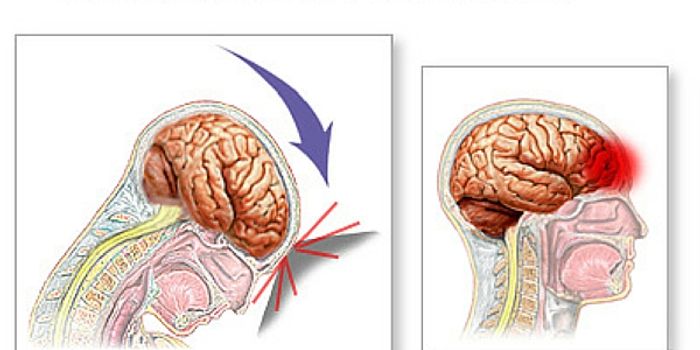

JUN 07, 2016NeuroscienceA traumatic brain injuries, or TBI, can be devastating and have long-lasting effects. In children these injuries can be ...

JUN 01, 2016NeuroscienceThe saga of the NFL and its responsibility for traumatic brain injuries to players continued this week with a report fro ...

MAY 12, 2016NeuroscienceTraumatic brain injuries, or TBI, are known to cause a variety of problems. TBI has been indicated in Chronic Traumatic ...

MAR 23, 2016NeuroscienceWhile the subject of brain injuries, concussion and Chronic Traumatic Encephalopathy (CTE) have swirled around the NFL f ...